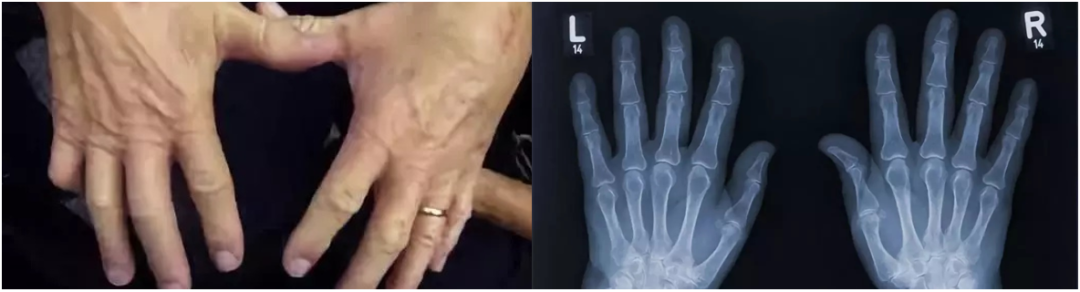

而 50 年后,他两只手的状态,无论是肉眼所见还是 X 光影像,并没有任何差别,都很健康。

图片来源:网络